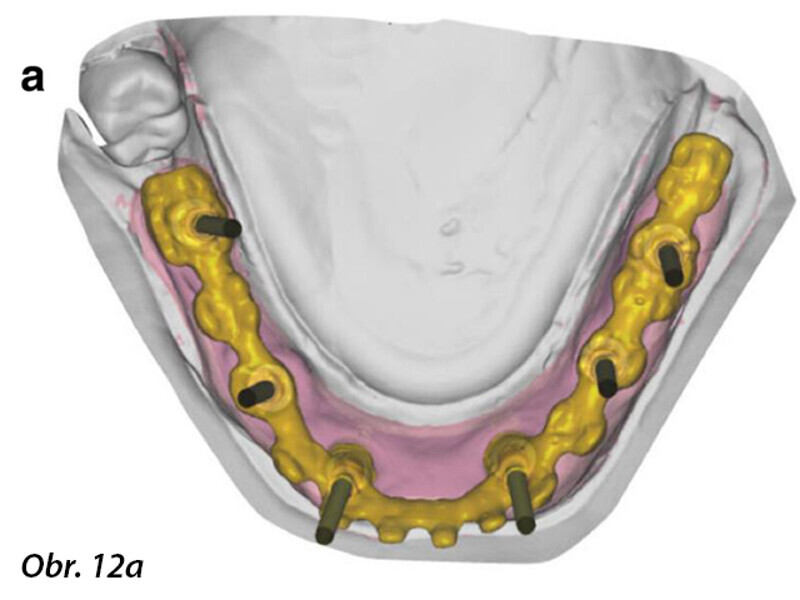

Počítačem asistované, šablonou se řídící okamžité zavedení a zatížení implantátu v dolní čelisti